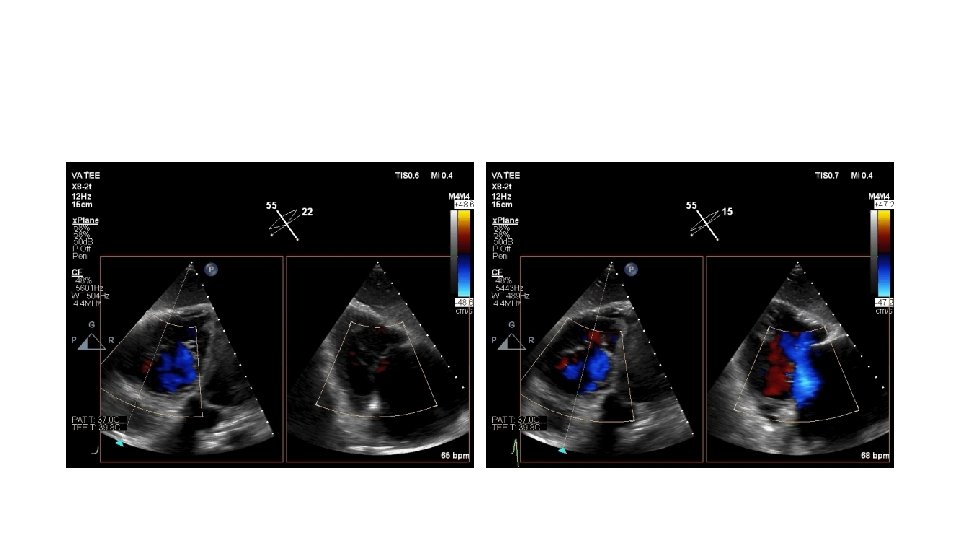

Tricuspid Valve (TV) Imaging • TV imaging is challenging • Three TV leaflets (anterior, septal and posterior) are thin and membranous Huitin et al. Archives of Cardiovascular Diseases Volume 109, Issue 1, January 2016, Pages 67 -80

• TV assessment • severity of TR • Mechanism of • mode of leaflet coaptation, • degree of tricuspid annulus enlargement and tenting • TAPSE • 3 D-TEE • Cardiac CT • cardiac MRI